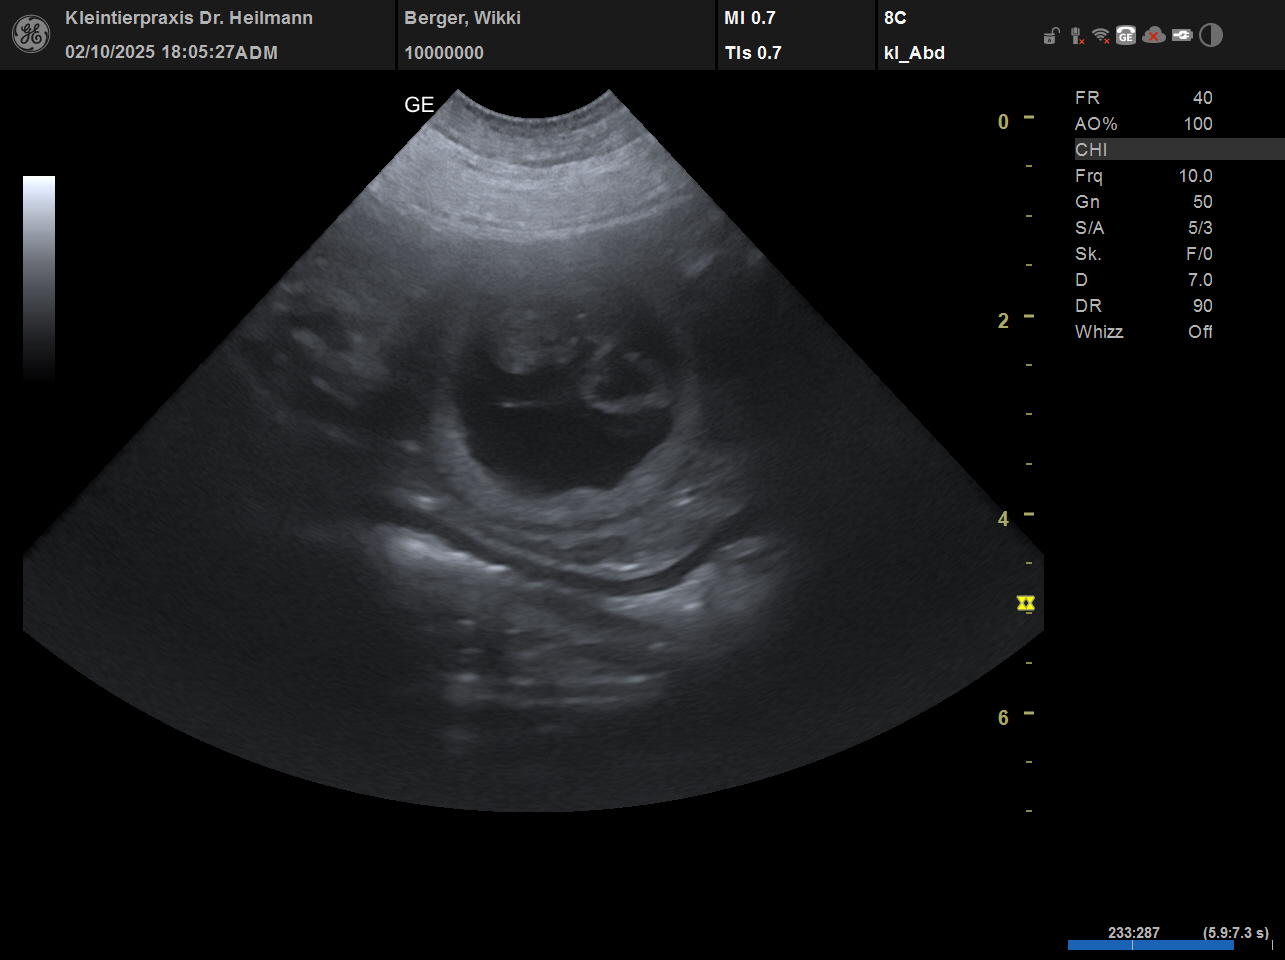

WIKKI BEKOMMT WELPEN

Wir waren beim Ultraschall. [Mehr lesen…]